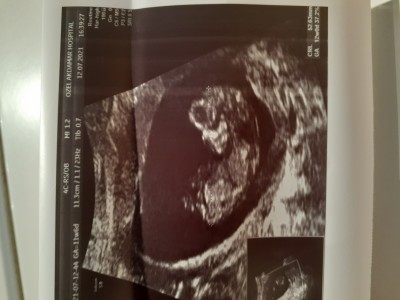

Çok hareketli, doktor cinsiyetini bir türlü göremiyor. Lütfen bakar mısınız? Her gidişimde bir umut gidiyorum

image